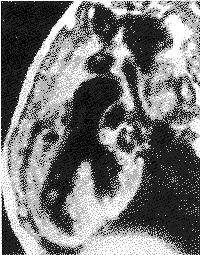

主动脉骑跨 在心脏长轴位上做向头侧成角的斜位像或垂直于室间隔左室短轴位上均能清楚显示增宽的主动脉骑跨缺损的室间隔上(图2),cine-MRI显示主动脉骑跨情况与CAG侧位或左前斜位显示相类似(图3),测量骑跨率与UCG及CAG测量结果相一致(P>0.05)。

图2 在心脏长轴位向头侧成角的斜位像

显示增宽的主动脉骑跨在室间隔上,骑跨率50%

图3 垂直于室间隔短轴位电影MRI示升主动脉骑跨

于室缺之上,收缩中期见左右心室血液同时射向

主动脉,与心血管造影左前斜位相似